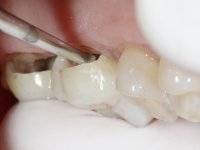

Teeth 17 and 16 were prepared for the fabrication of a 2-element Zr bridge. The impression was performed with a double mixing technique and a monolithic bridge in Zr was made in the laboratory. 4 years later, an abscess appeared in the apical area of tooth 26. It was decided to remove the bridge, remove the intra-radicular posts and retract the endodontic treatments of teeth 17 and 16. The removal of the bridge was carried out by making two cervical cavities. in the palatal area of the bridge and with a microluxator, disinsertion movements were performed. The intra-radicular posts were removed using fine drills and an ultrasound tip. The bridge was provisionally cemented and the patient was referred to a fellow endodontist for endodontic retreatment. After the retreatment, the intraradicular posts were placed again and the bridge was definitively cemented. One year later, a new abscess appears, possibly related to a root fracture. The bridge was sectioned between tooth 27 and 26 and tooth 26 was extracted and the crown of 27 was provisionally cemented. 3 months later, teeth 27 and 25 were prepared and a temporary bridge was made in dual polymerization resin. Then, an impression was made using the double mixing technique and a 3-element bridge in Zr was made in the laboratory. It was permanently cemented in the mouth with resin-reinforced glass ionomer cement.